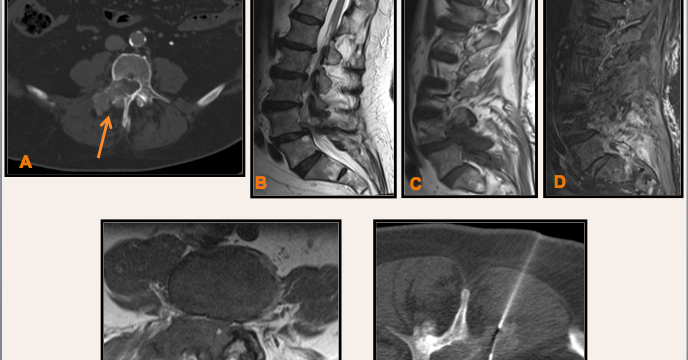

Historia Clínica

Niño de 4 años en estudio por crisis comiciales.